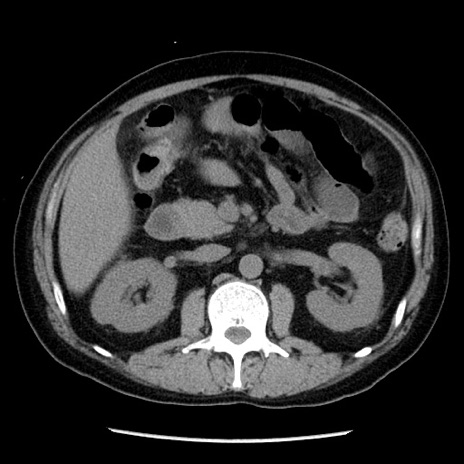

症例29(横断像)

【症例】40歳代男性

【現病歴】2日前から胃痛あり。徐々に周期的な激痛に変化した。本日になっても激痛があるため受診。

【身体所見】意識清明、BT 38-39℃台あり、腹部:膨満、やや硬、右下腹部に圧痛あり。

【データ】WBC 8500、CRP 23.26